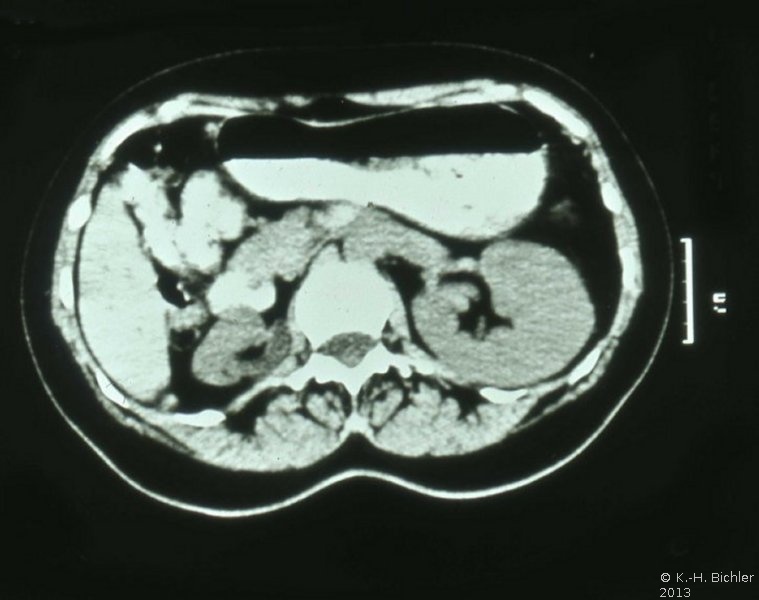

Computertomographie zur Diagnostik der kleinen Niere. Zum Beispiel eine pyelonephritisch veränderte linke Niere im Computertomogramm und im weiteren Beispiel CT und Organpräparat einer rechtsseitigen kleinen Niere.

Und in einem weiteren Beispiel CT und Organpräparat einer rechtseitigen "kleinen Niere" (Abbildung 11, 12ab).